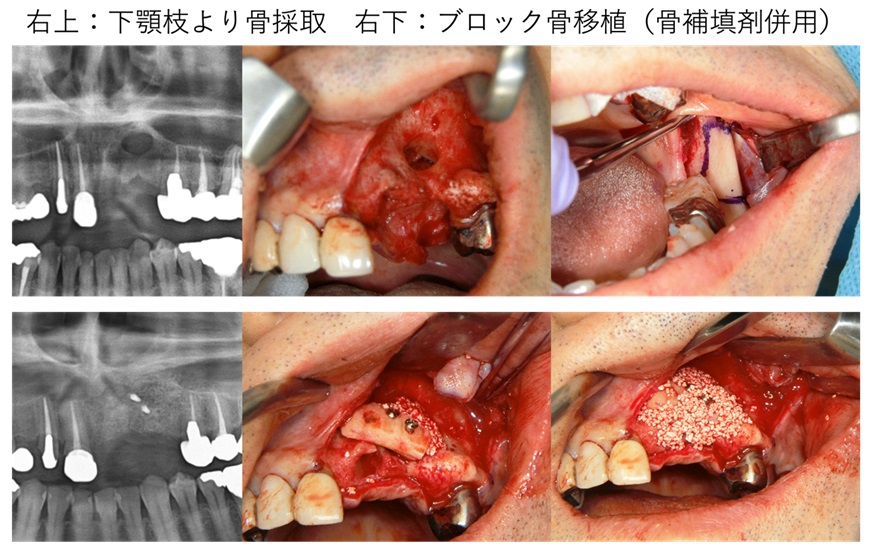

症例③ 上顎前歯部の歯槽骨欠損に対してブロック骨移植を行なった治療例。